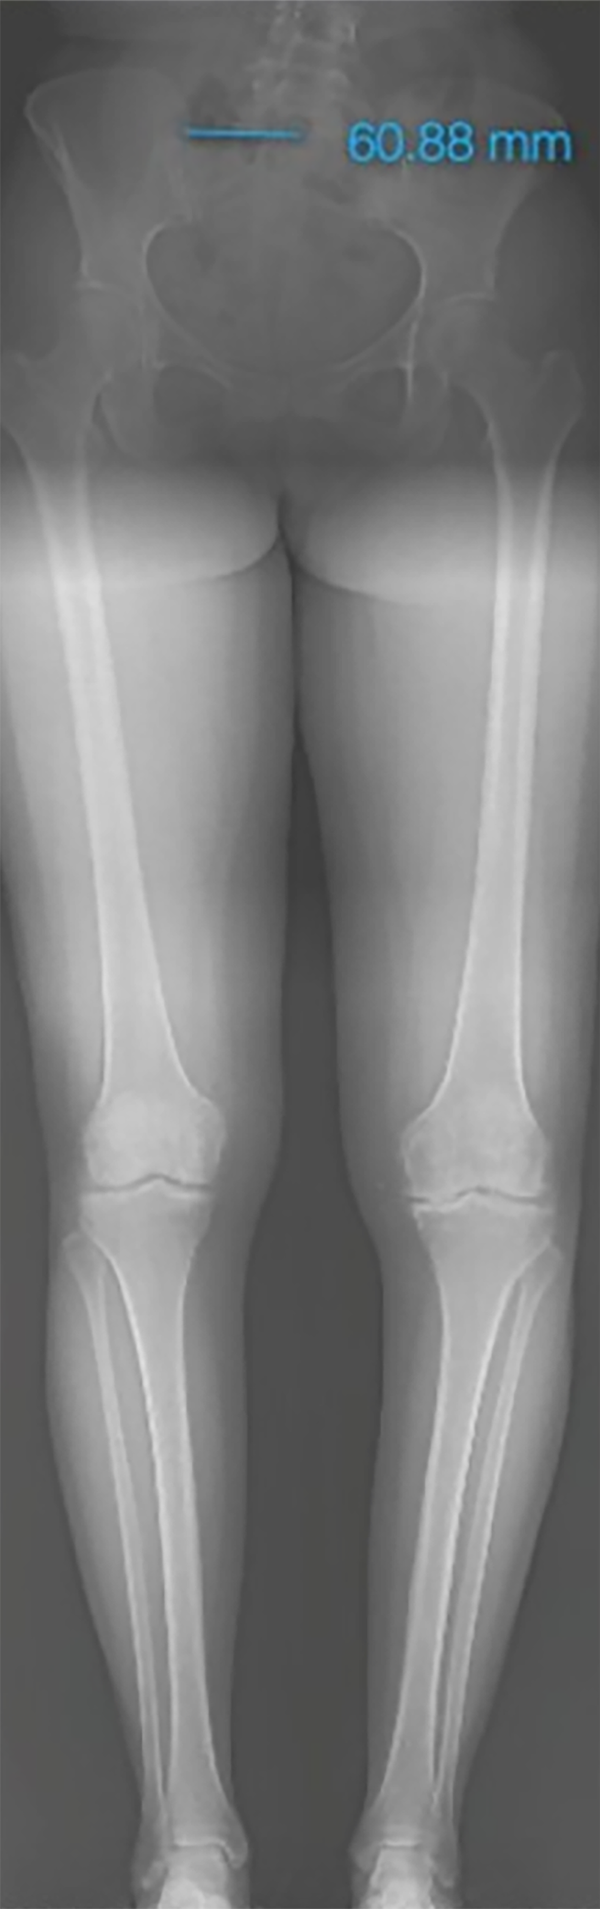

El paso 0 consiste en trazar una línea que va del centro articular de la cadera al centro articular del tobillo, recibe el nombre de “eje mecánico del miembro inferior” y el resultado fisiológico de esta medición es una línea que debe cruzar el centro articular de la rodilla con un rango de normalidad de desviación de 3 mm hacia medial o lateral.10 Al realizar la medición de la desviación, esta medida va a recibir el nombre de desviación del eje mecánico (MAD, por su nombre en inglés), según el cual, en caso de superar los 3 mm hacia medial, se trata de una deformidad en varo con un aumento de la carga en el compartimento medial de la rodilla; cuando el MAD se encuentra superior a los 3 mm laterales, es una deformidad en valgo y aumenta la carga del compartimento lateral de la rodilla21 (fig. 3).

Figura 3: Test de mal alineamiento: las líneas rojas corresponden al eje mecánico de los miembros inferiores, se marca el centro articular de la rodilla y se observa la desviación del eje mecánico o MAD derecho hacia medial de 24 mm, y en el izquierdo de 31 mm hacia medial, se evidencia una alteración de este valor con una deformidad en varo bilateral, con mayor predominio del lado izquierdo.